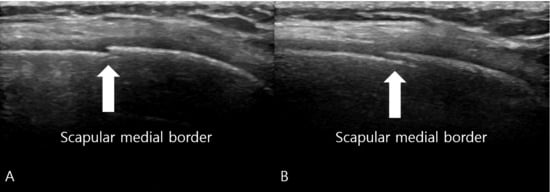

Figure 2. Musculoskeletal Ultrasound of the Right Scapula. (A) Longitudinal view obtained directly over the medial border of the scapula reveals a subtle cortical irregularity (white arrow) indicating the fracture site, which was not visible on plain radiographs. (B) Longitudinal view obtained medial to the scapular border demonstrates a more extensive cortical disruption with a longer fracture line (white arrow), confirming the location of point tenderness and providing additional evidence of the stress fracture. The sonographic finding of cortical disruption, combined with focal tenderness on sonopalpation, led to a provisional diagnosis of a scapular stress fracture.

Radiographs, including true anteroposterior, Y, and axillary views, showed no abnormality [Figure 1], but the MSK ultrasound revealed cortical irregularity in the right scapular body, corresponding to the site of pain. Two distinct longitudinal views were obtained: one directly over the medial scapular border showing a subtle cortical irregularity, and another medial to the border revealing a more extensive cortical disruption with a longer fracture line [Figure 2]. Sonoguided digital palpation was performed, and localized tenderness was observed at the site of cortical irregularity, leading to a provisional diagnosis of scapular fracture. The chronological sequence of clinical events, diagnostic imaging, and interventions is summarized in Table 1. Following the suspicion of a scapular fracture, treatment focused on both potential fracture healing and the restoration of scapular stability [21]. Prolotherapy injections were administered to the right scapular medial border and surrounding ligaments to promote structural stability. Prolotherapy was administered using a solution of 10% dextrose. Under ultrasound guidance, approximately 5 mL of the solution was injected into the periosteum and surrounding tendons at the site of cortical irregularity on the medial scapular border. This procedure was repeated bi-weekly for a total of 4 sessions over two months.